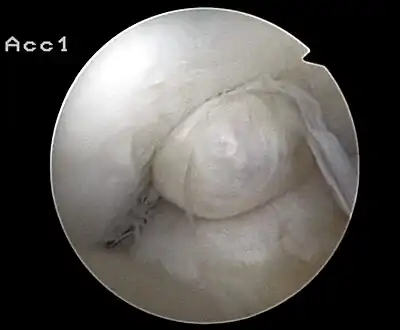

Arthroscopie diagnostique

La sécurité diagnostique la meilleure est obtenue par arthroscopie diagnostique. Ce procédé représente l'étalon-or pour le diagnostic de la rupture de LC. Ce procédé relève d'une chirurgie invasive au minimum, mais comporte certains risques, comme toute intervention chirurgicale dans le genou du patient[116]. Comme cependant le traitement chirurgical d'une rupture de LC sera conduit par chirurgie arthroscopique, il est possible d'enchaîner celle-ci immédiatement après l'arthroscopie diagnostique, par la résection partielle du ligament (pour une déchirure) ou la reconstruction en cas d'arrachement. Avec l'accroissement de la facilité de l'IRM, le nombre d'arthroscopies purement diagnostiques a nettement diminué ces dernières années[117],[118]. L'arthroscopie diagnostique est quand même utilisée comme précédemment comme procédé de choix pour une compréhension certaine du diagnostic de rupture de LC, en cas d'examen clinique confus et d'IRM difficile à interpréter[116].